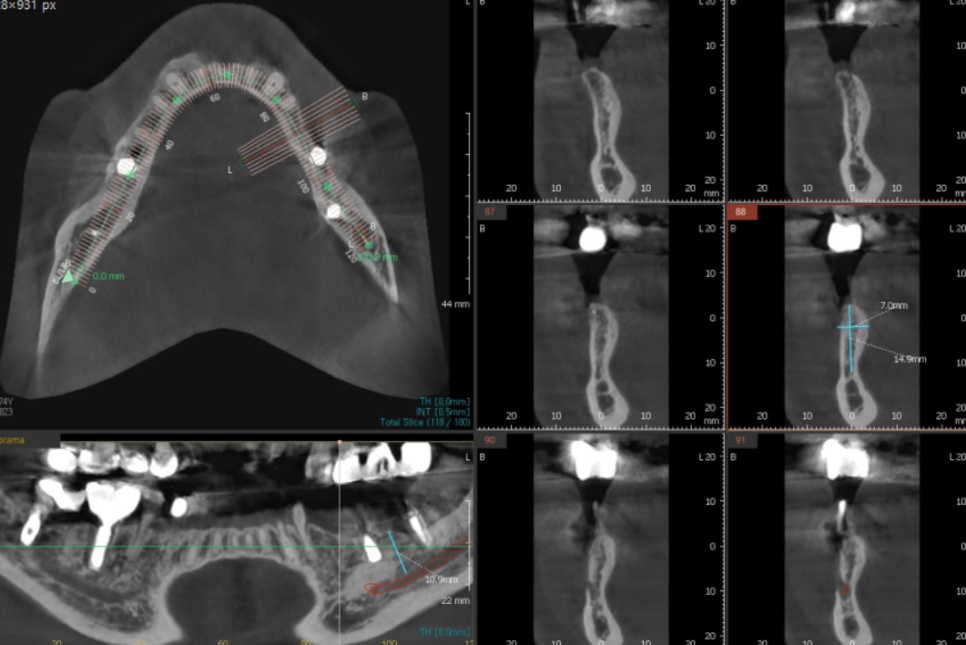

위아래 양쪽으로 치료를 하신 환자분

잇몸뼈가 전반적으로 많이 녹기도 하였고

오래 전 한 보철이 문제가 있엇습니다.

환자분은 왼쪽 아래 오래전에 한 임플란트가

들썩 들썩 흔들려서

식사를 못하고 계신다 하셨습니다.

23.08.23

망월동 치과에서 발치후

왼쪽 아래 임플란트 먼저 수술하였습니다.

재수술인셈이죠.

기존에 있는 임플란트를 제거 후

교체해주는 작업을 진행하였습니다.